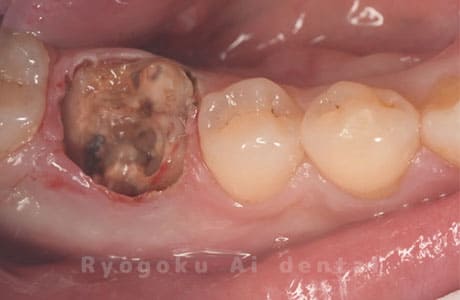

Case02

-

- 原因

- C4

- 治療期間

- 3ヶ月

- 治療内容

- 自家歯牙移植手術+マイクロエンド+ダイレクトボンディング

- 治療費用

- 220,000円

他院で虫歯が大きく、抜歯と判断され、インプラント手術を提案された患者様です。親知らずが残存していたため、自家歯牙移植手術を行いました。

<リスク・副作用>

治療後、痛みや違和感、出血、腫れなどが出る事があります。喫煙者、糖尿病などの方の場合、歯が生着しない場合があります。